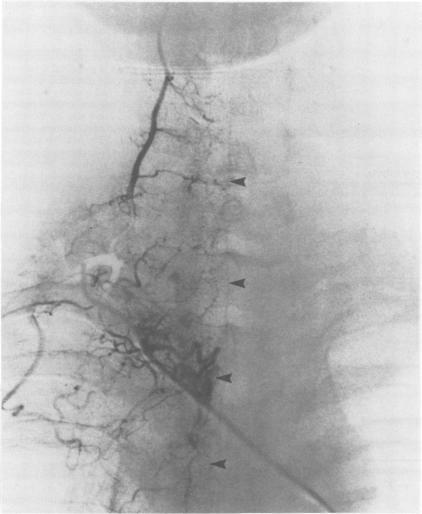

Jiménez-Jiménez F J, Garzo-Fernández C, De Inovencio-Arocena J, Pérez-Sotelo M, Castro-De Castro P, Salinero-Paniagua E

J Neurol Neurosurg Psychiatry. 1991 Mar;54(3):281-2. doi: 10.1136/jnnp.54.3.281.